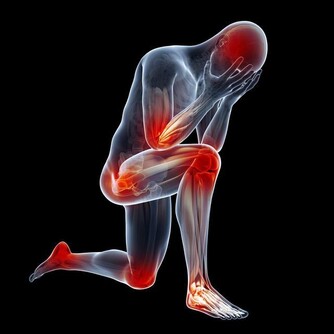

為什麼呢?因為喝了很多水,但不能及時排出去的話,會形成水腫,甚至會加重病情。

在患者的想像中,如果腎臟生了病,出現了腎炎,就應該小心使用,

而大量喝水,無疑會加重腎臟負擔,所以腎病患者喝水時都小心翼翼。